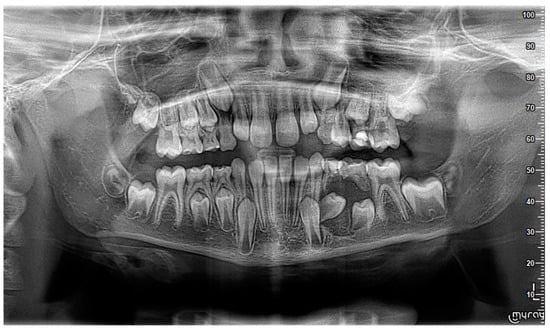

2. Case Report